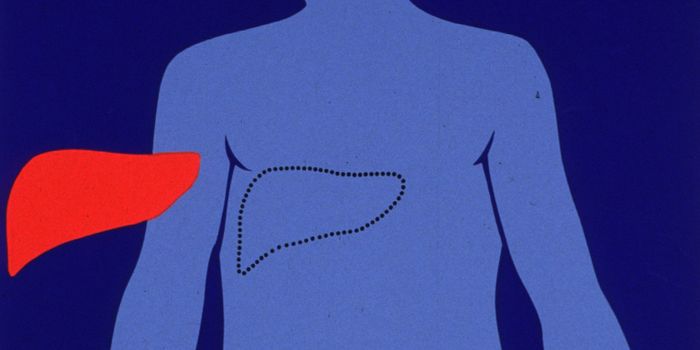

JAN 04, 2024CancerThe most common type of adult liver cancer, hepatocellular carcinoma (HCC), accounts for about 90% of liver cancer diagn ...